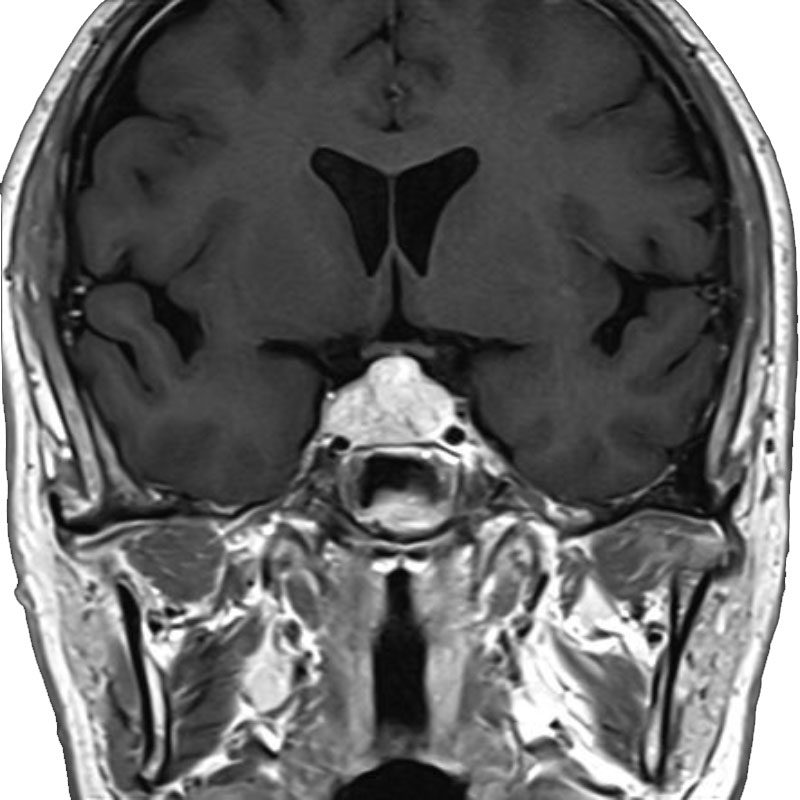

脳動静脈奇形

摘出術

南田/野本/元永